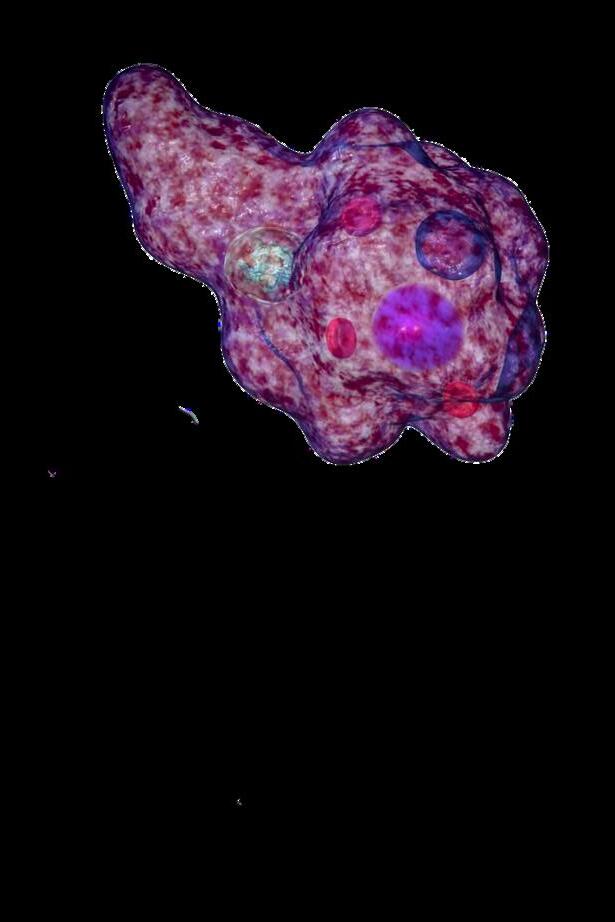

TROFOZOITO

Microorganismo piriforme ameboide

Tamaño: Fluctúa entre 11-16 µm

Posee un núcleo vesicular central de 2 a 4 µm

Posee un forma variable (ameboide)

Tiene pseudópodos cortos y gruesos que le permiten moverse y fagocitar partículas alimentarias.

Se caracteriza por presentar un cariosoma de gran tamaño y una gran vacuola

QUISTE

Forma esférica u oval.

Mide de 5-20 µm.

De forma redondeada y circular.

Contiene de 1 núcleo con cromatina abundante , dependiendo de la madurez del quiste.

Presenta 1 o 2 vacuolas